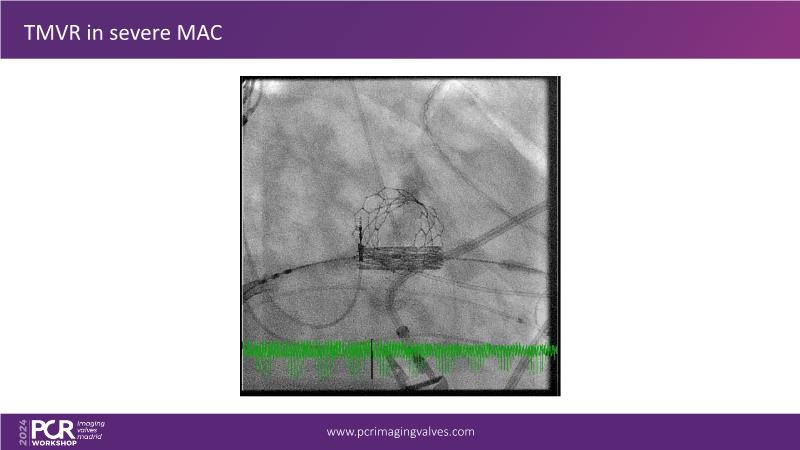

Explore cutting-edge transcatheter valve interventions for mitral and aortic valve disorders, including valve-in-valve procedures and management strategies for paravalvular leakages, and learn about diagnosing and treating mitral annular calcification and transcatheter options in infective endocarditis.

- To get tips and tricks for guidance of transcatheter intervention